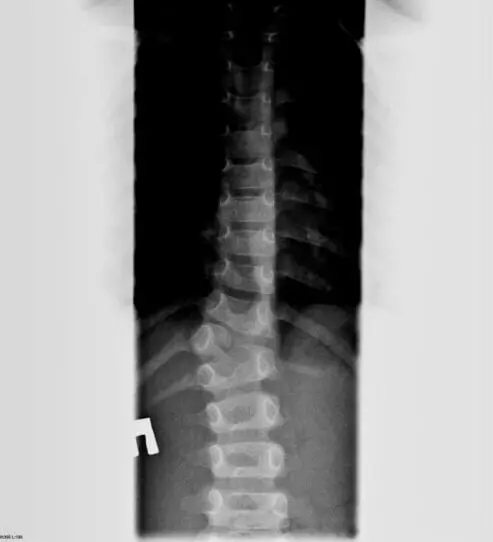

К врожденным относят сколиозы, которые возникают на фоне аномалий внутриутробной закладки и развития позвонков, межпозвоночных дисков, суставов позвоночника. Например, клиновидная деформация позвонков, как показано на рисунке ниже.

Поэтому так важна рентгенография, которую мы проводим при диагностике сколиоза.

Рентгенологически определяют 4 степени сколиоза: І степень – угол деформации до 5 градусов, ІІ степень – от 6 до 25 градусов, ІІІ степень – от 26 до 50 градусов, ІV степень – угол деформации более 50 градусов.